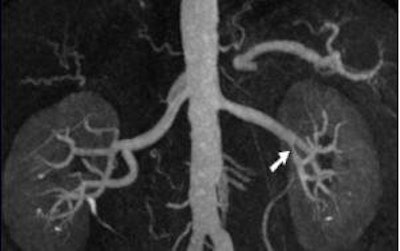

| Coronal oblique 3D volume rendered (above) and thin MIP (below) from CEMRA, in a 60-year-old woman with uncontrolled hypertension, show beaded irregularity involving the distal right renal artery (arrows) consistent with fibromuscular dysplasia (FMD). Images courtesy of Dr. Kambiz Nael. |

![]() |